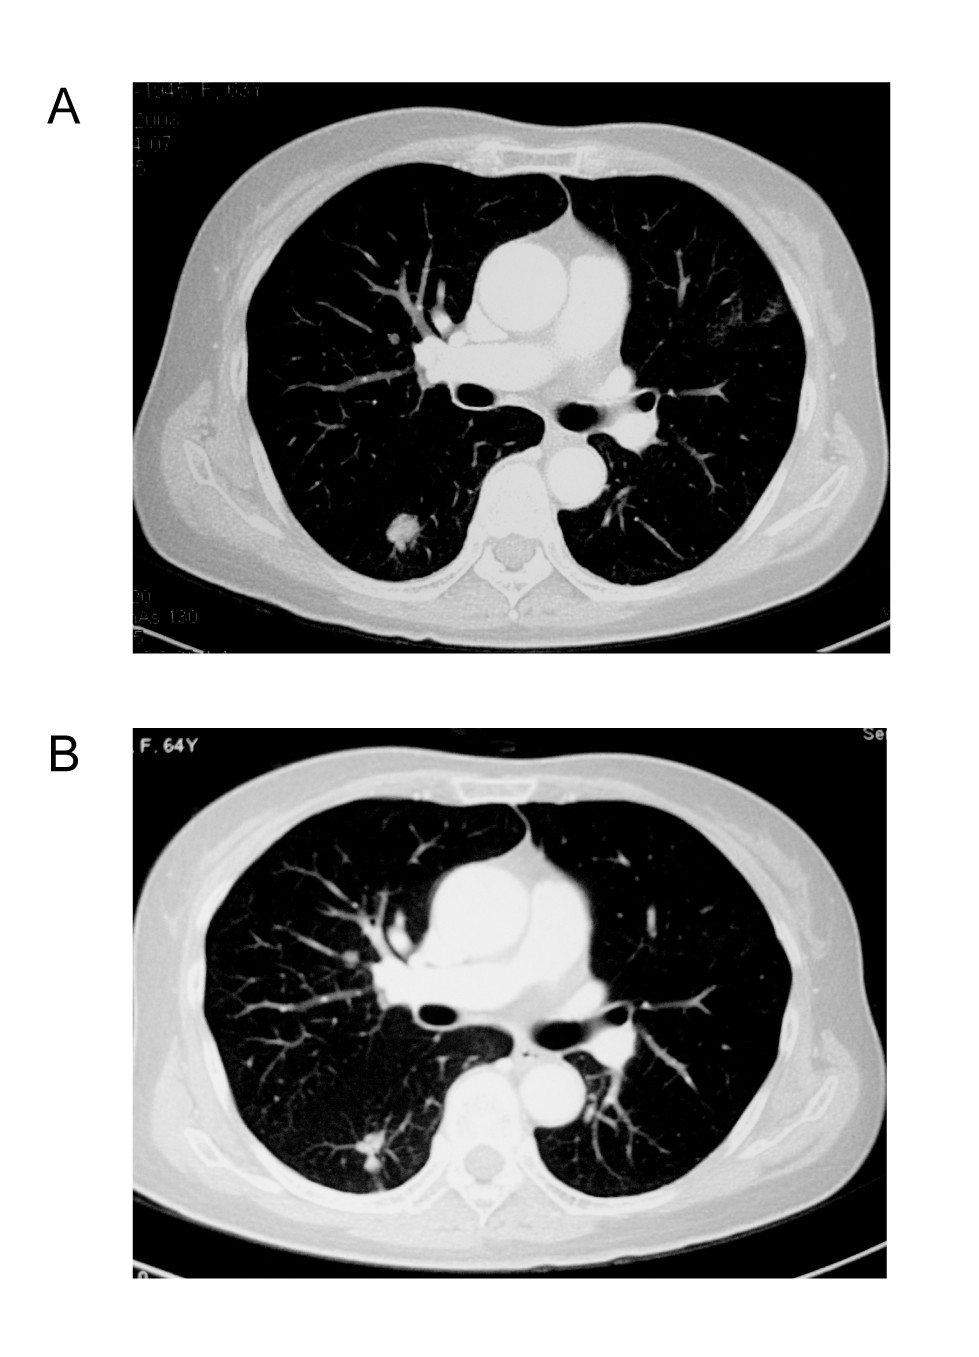

A 65-year-old female with metastatic rectal cancer involving the liver and lung, had prior treatment with 3 cycles of liver chemoembolization and 2 cycles of FOLFOX4 regimen, who refused further chemotherapy, treated at 750 mg qd dose level had a partial response. Compared with the baseline CT-scan, the same lesions on day 60 showed more than 30% decrease in the sum of the longest diameter. Further CT-scan confirmed partial response. The patient received 750 mg qd until disease progression (on day 215). Figure 2

Figure 2

Tumor shrinkage was confirmed (B) after 4 months of treatment with apatinib comparing with baseline (A).